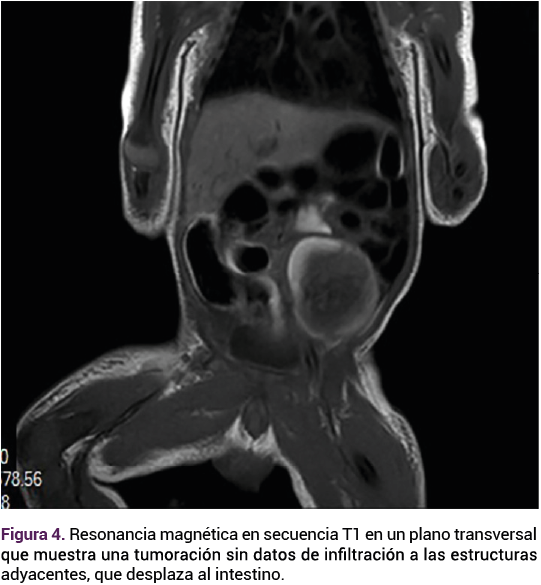

Ante las características ecográficas de la tumoración se decidió la conducta expectante, con seguimiento ecográfico. A las 37 semanas el feto continuaba con una frecuencia cardiaca de 140 lpm, peso de 3186 g, percentil 84, placenta fúndica, líquido amniótico cualitativamente normal. Sin embargo, con un aumento notable del tamaño de la tumoración intraabdominal, ahora 1 cm más grande, respecto del rastreo previo.

<strong>Figura 3</strong>

Figura 3.